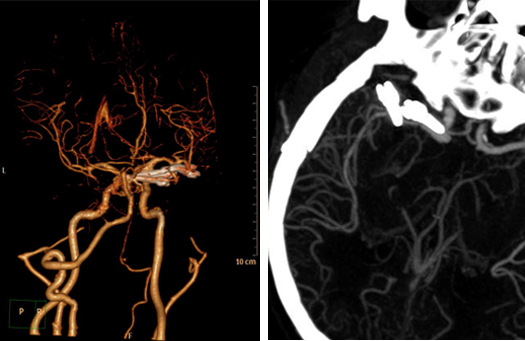

吾主任术后点评:颅内存在两个或两个以上的动脉瘤,称为多发动脉瘤,无论诊断及治疗都要难于单发动脉瘤,与单一动脉瘤相比,处理多发动脉瘤首先应明确哪个是导致出血的责任动脉瘤,破裂动脉瘤出血再次出血机会更多,如果对责任病灶判断错误,术后发生再出血概率高。此例病人为右侧颈内动脉及右侧大脑中M1段动脉瘤,依据头颅CT蛛网膜下腔出血范围及聚集部位判断右侧大脑中M1段为责任动脉瘤,右侧颈内动脉瘤直径大于50px,大型动脉瘤;手术从右侧翼点入路,首先分离侧裂处理大脑中的责任动脉瘤,需注意保护豆纹动脉,然后处理颈内动脉大型动脉瘤,需保护脉络膜前动脉、后交通动脉,后方注意保护动眼神经,避免术后偏瘫、偏身障碍、眼睑下垂等症状;术后病人取得良好的效果,一次开颅夹闭两个颅内动脉瘤,手术损伤小,患者恢复快,术后12天办理出院,肢体功能良好。术后复查头颅CTA检查动脉瘤不显影,远端血管显影良好。

术后CTA